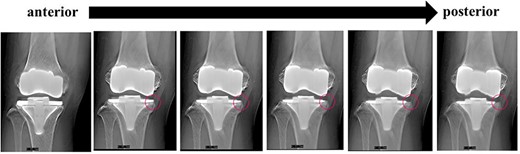

A preoperative standing anteroposterior plain radiograph of the right knee showed a hip-knee-ankle angle of 14 varus alignment (Fig. 1). Preoperative lateral plain radiographs showed posterior subluxation of the femoral component at 10 years after surgery (Fig. 2). Preoperative varus and valgus stability of the knee joint in extension were assessed with stress radiography using a Telos arthrometer (Telos SD 900 Stress Device; Telos Medical Co., Ltd, USA). The patient was instructed to lie supine on a table for the measurement. During varus and valgus stress testing, a force of 150 N was applied just above the joint on the lateral or medial femoral condyle to test for varus or valgus instability (Fig. 3) [8]. Cross-sectional anteroposterior imaging using Tomosynthesis-Shimadzu metal artifact reduction technology (T-smart) (Japan) showed tibial component subsidence at the medial tibial plateau (Fig. 4).

Post-operative anteroposterior and lateral plain radiographs. The γ angle was 82°. (a) Immediate after surgery, (b) 5 years after surgery, (c) 8 years after surgery, (d) 10 years after surgery.

In a study based on three-dimensional computed tomography, Yamagami et al. found that using a posterior tibial slope of more than 9° can damage the insertion of the semimembranosus tendon, resulting in rotatory instability [18]. In this patient, the tibial osteotomy was performed with a posterior tibial slope of 8° (Fig. 2) and UHMWPE (standard CR type) with a posterior slope of 3° was selected. The resulting 11° of posterior tilt resulted in UHMWPE wear and breakage of the posteromedial tibial baseplate at 10 years. In addition to the Standard CR, the Vanguard CR system also includes the CR Lipped and Anterior Stabilised types, which have flat articular surfaces. For patients with a large physiologic posterior tibial tilt, a standard CR prosthesis with a built-in posterior tilt of 3° should not be selected.